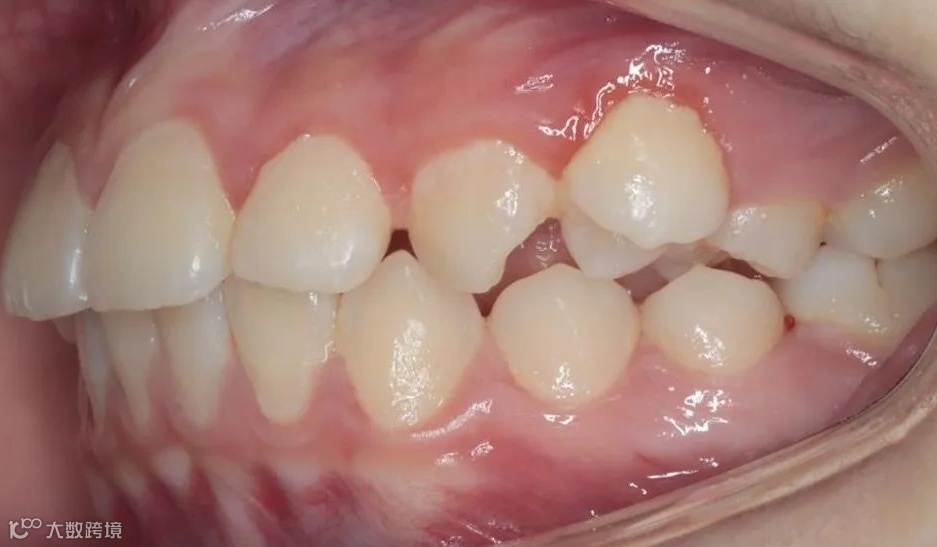

治疗前右侧咬𬌗相

治疗前正面向咬𬌗相

治疗前左侧咬𬌗相

患儿戴用Twin-Block矫治器,在引导下颌向前的同时扩宽上颌牙弓,内收上前牙。

治疗后右侧咬𬌗相

治疗后正面咬𬌗相

治疗后左侧咬𬌗相